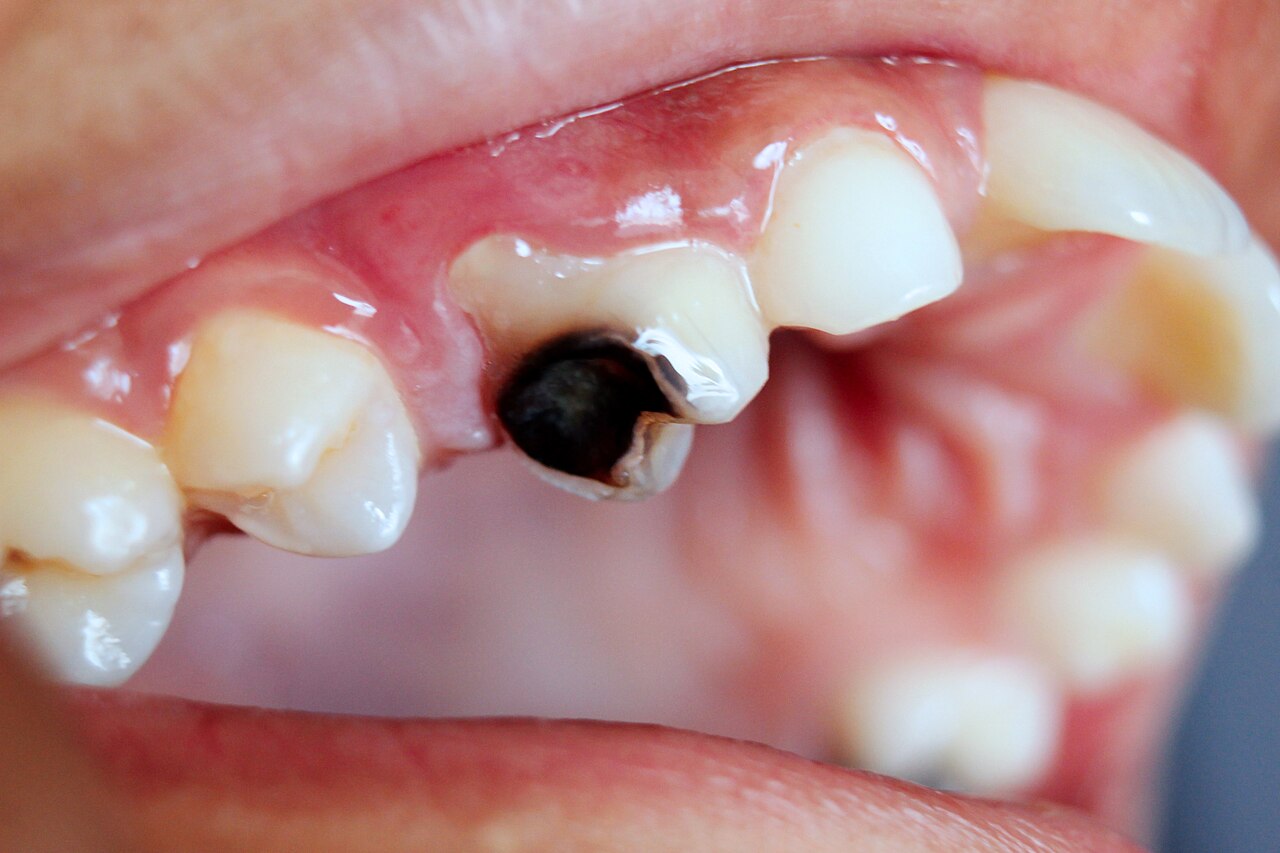

1. Carie profonde non traitee (cause #1)

C'est la cause de 60 a 70% des abces dentaires. Une carie est une destruction progressive de la dent par les acides produits par les bacteries (principalement Streptococcus mutans). Au debut, la carie est limitee a l'email (indolore, reversible par fluoration). Elle traverse ensuite la dentine (sensibilite au froid, au sucre). Si elle n'est pas soignee, elle atteint la pulpe : les bacteries penetrent dans la chambre pulpaire, provoquent une pulpite aigue (douleur violente) puis une necrose pulpaire, et enfin un abces peri-apical.